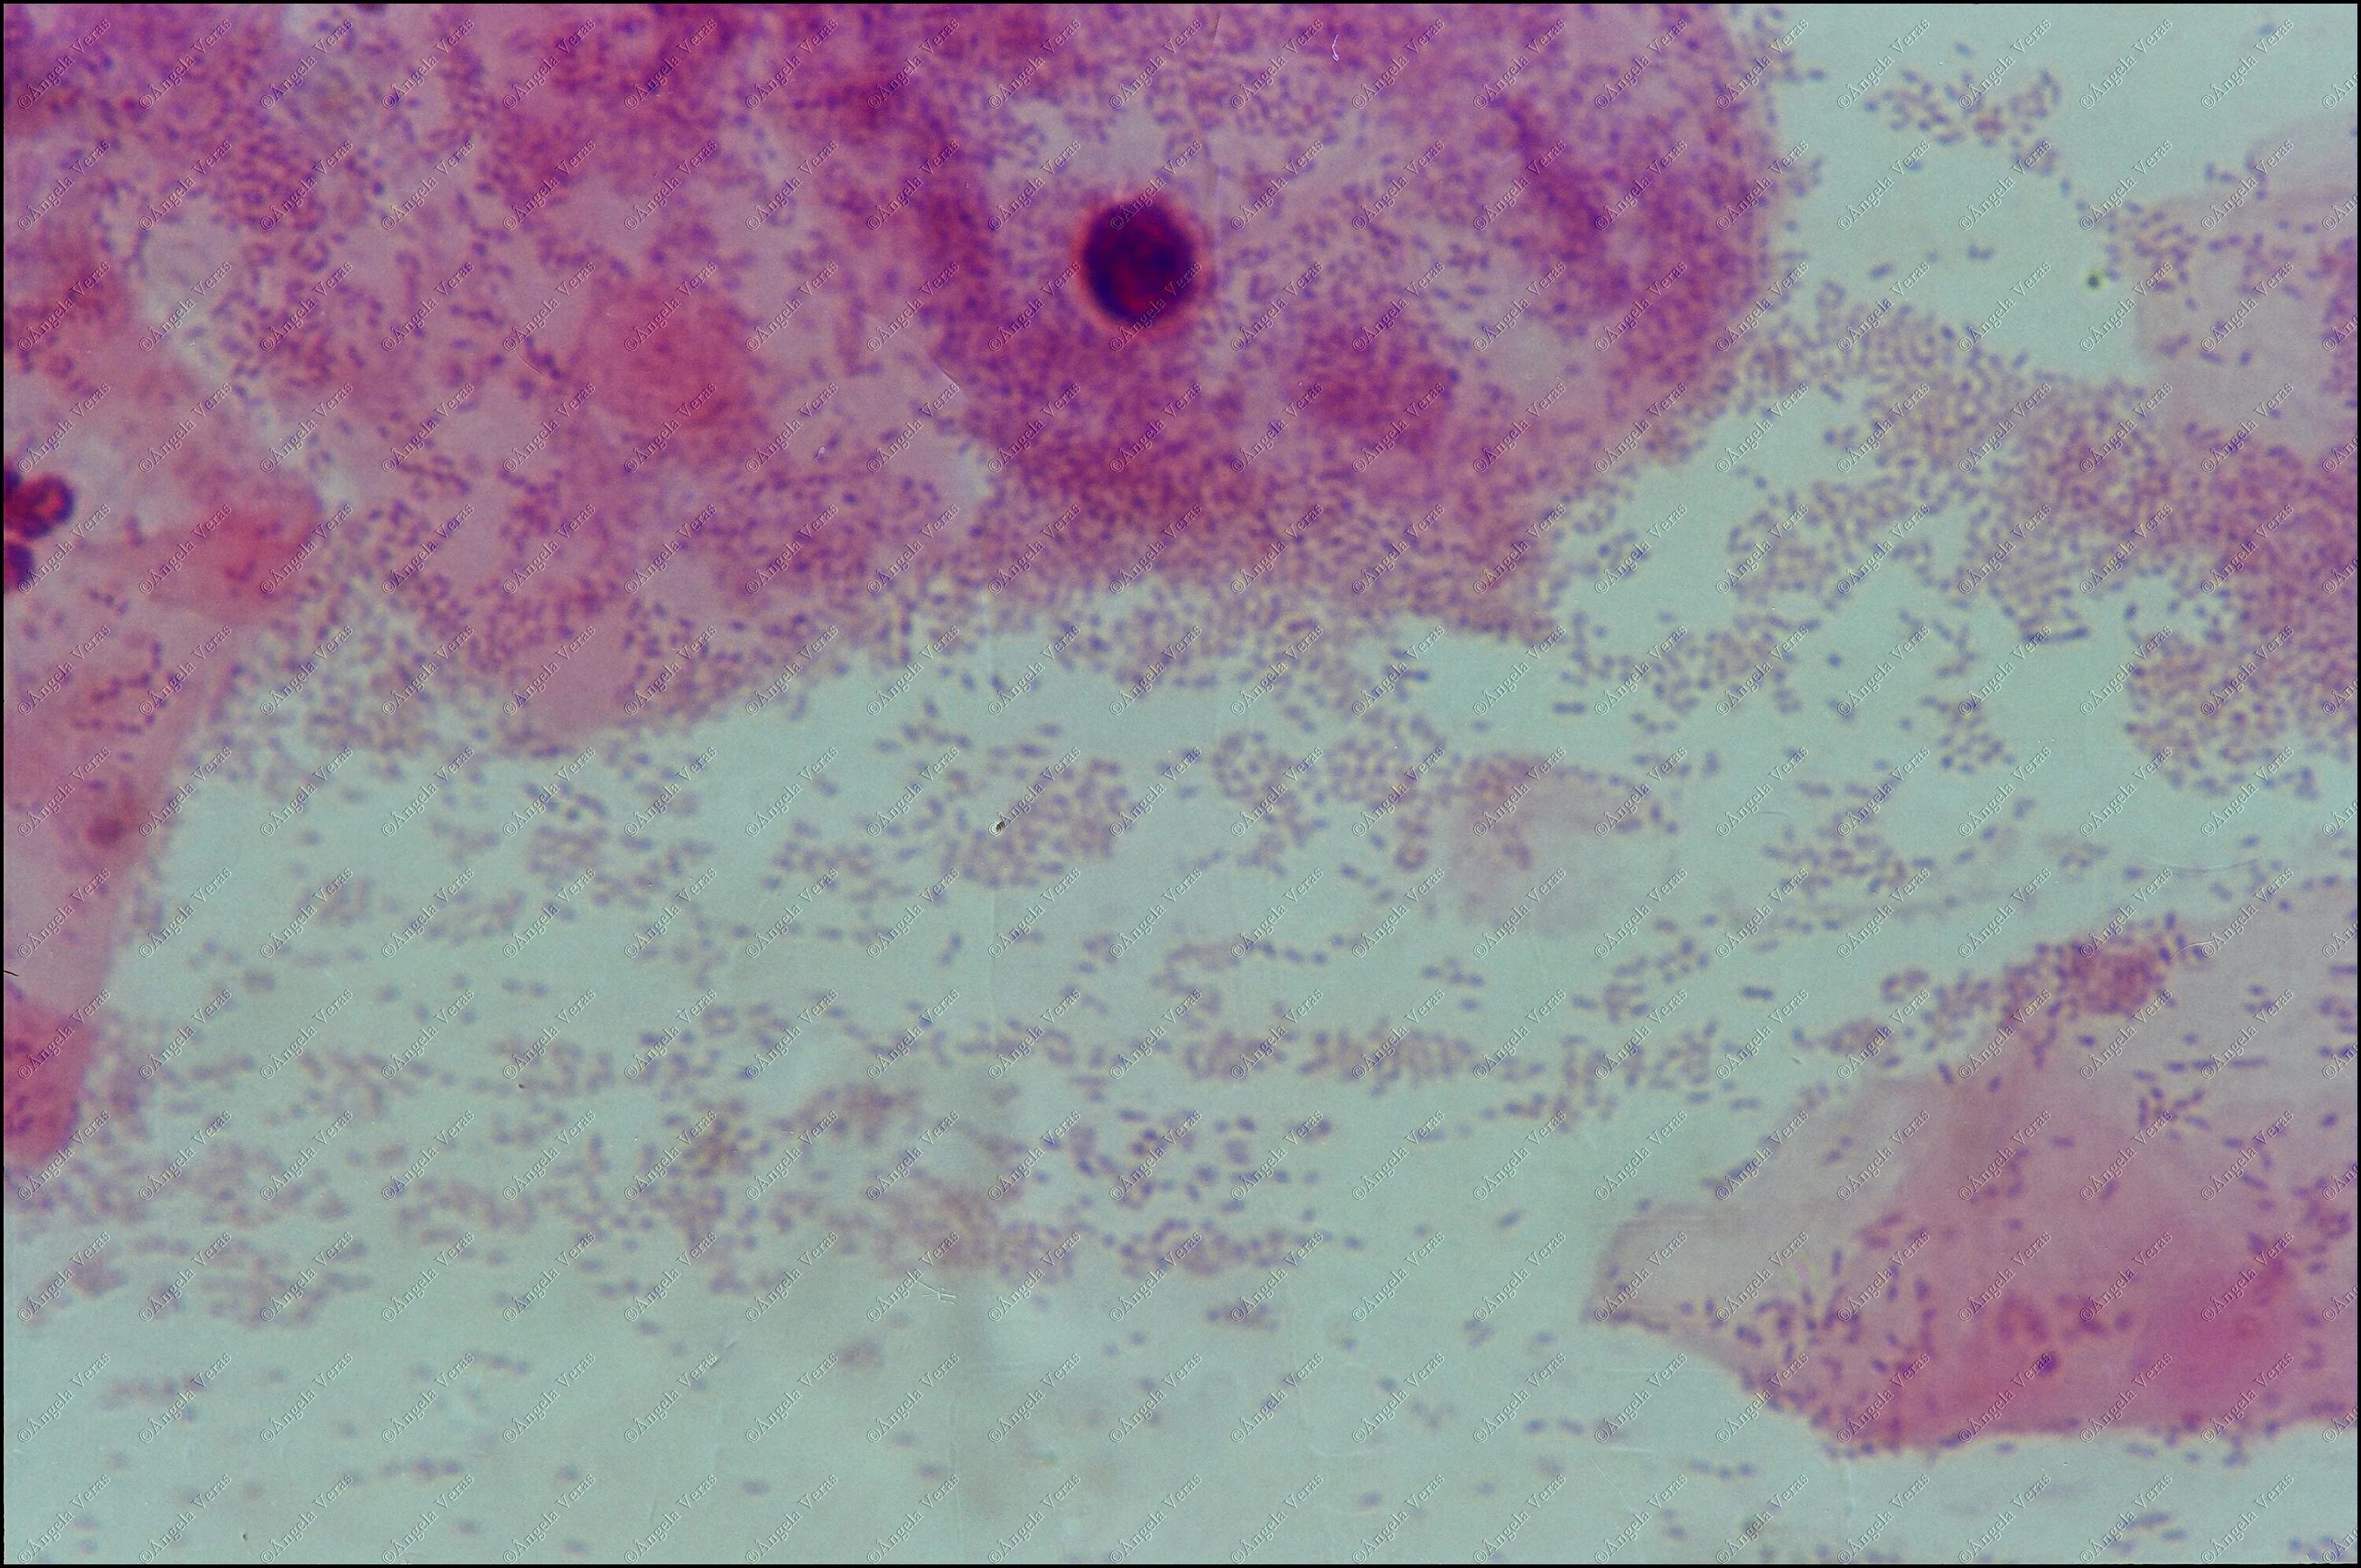

Микроскопия окрашенных